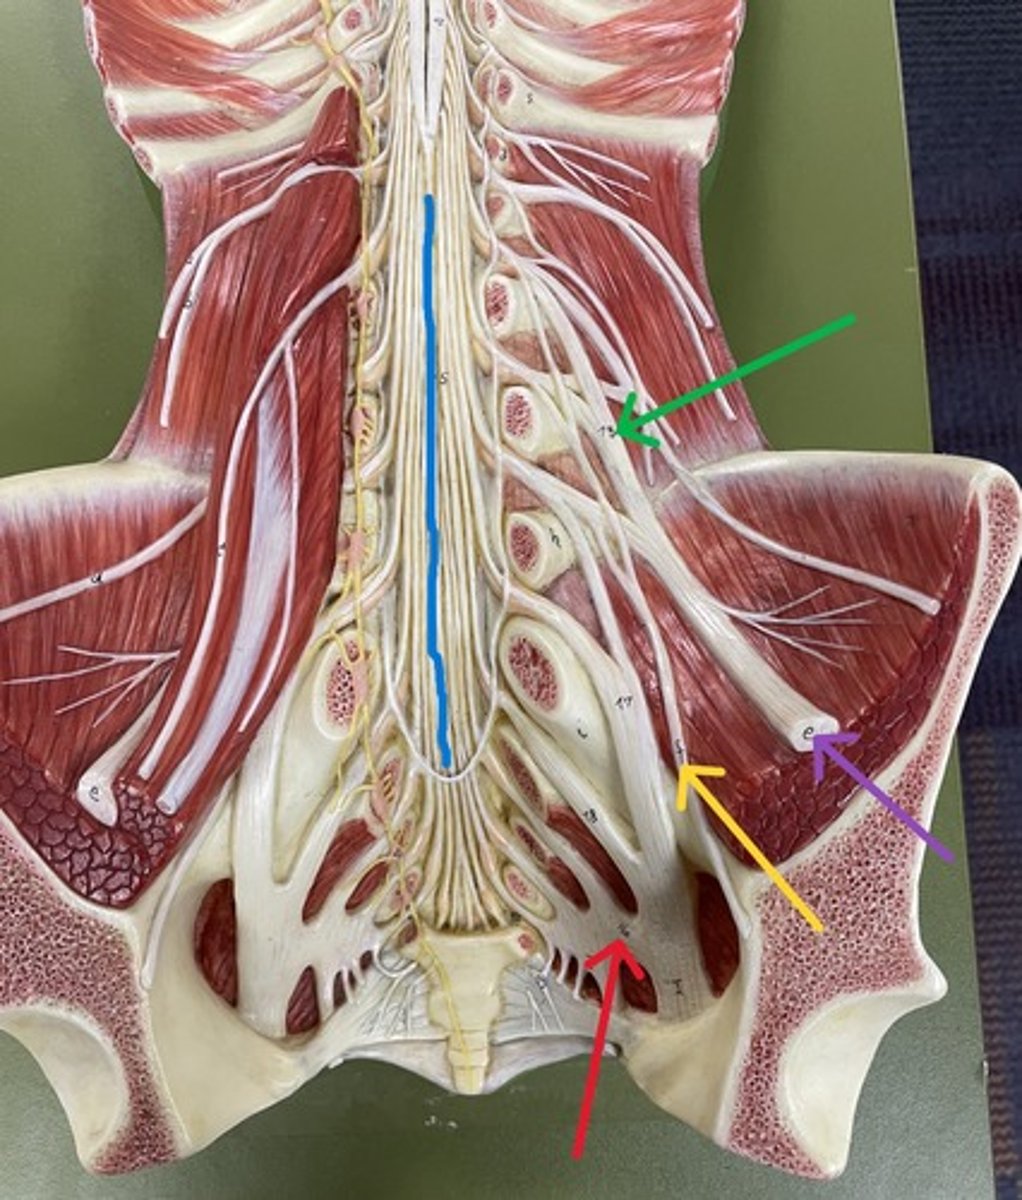

Filum terminale

blue

Lumbar plexus

Lumbar plexus

green

Femoral nerve

purple

Femoral nerve

blue

Obturator nerve

yellow

Obturator nerve

Sacral plexus

purple

Sacral plexus

red

Sciatic nerve

red

Tibial nerve

red

Common fibular nerve

blue